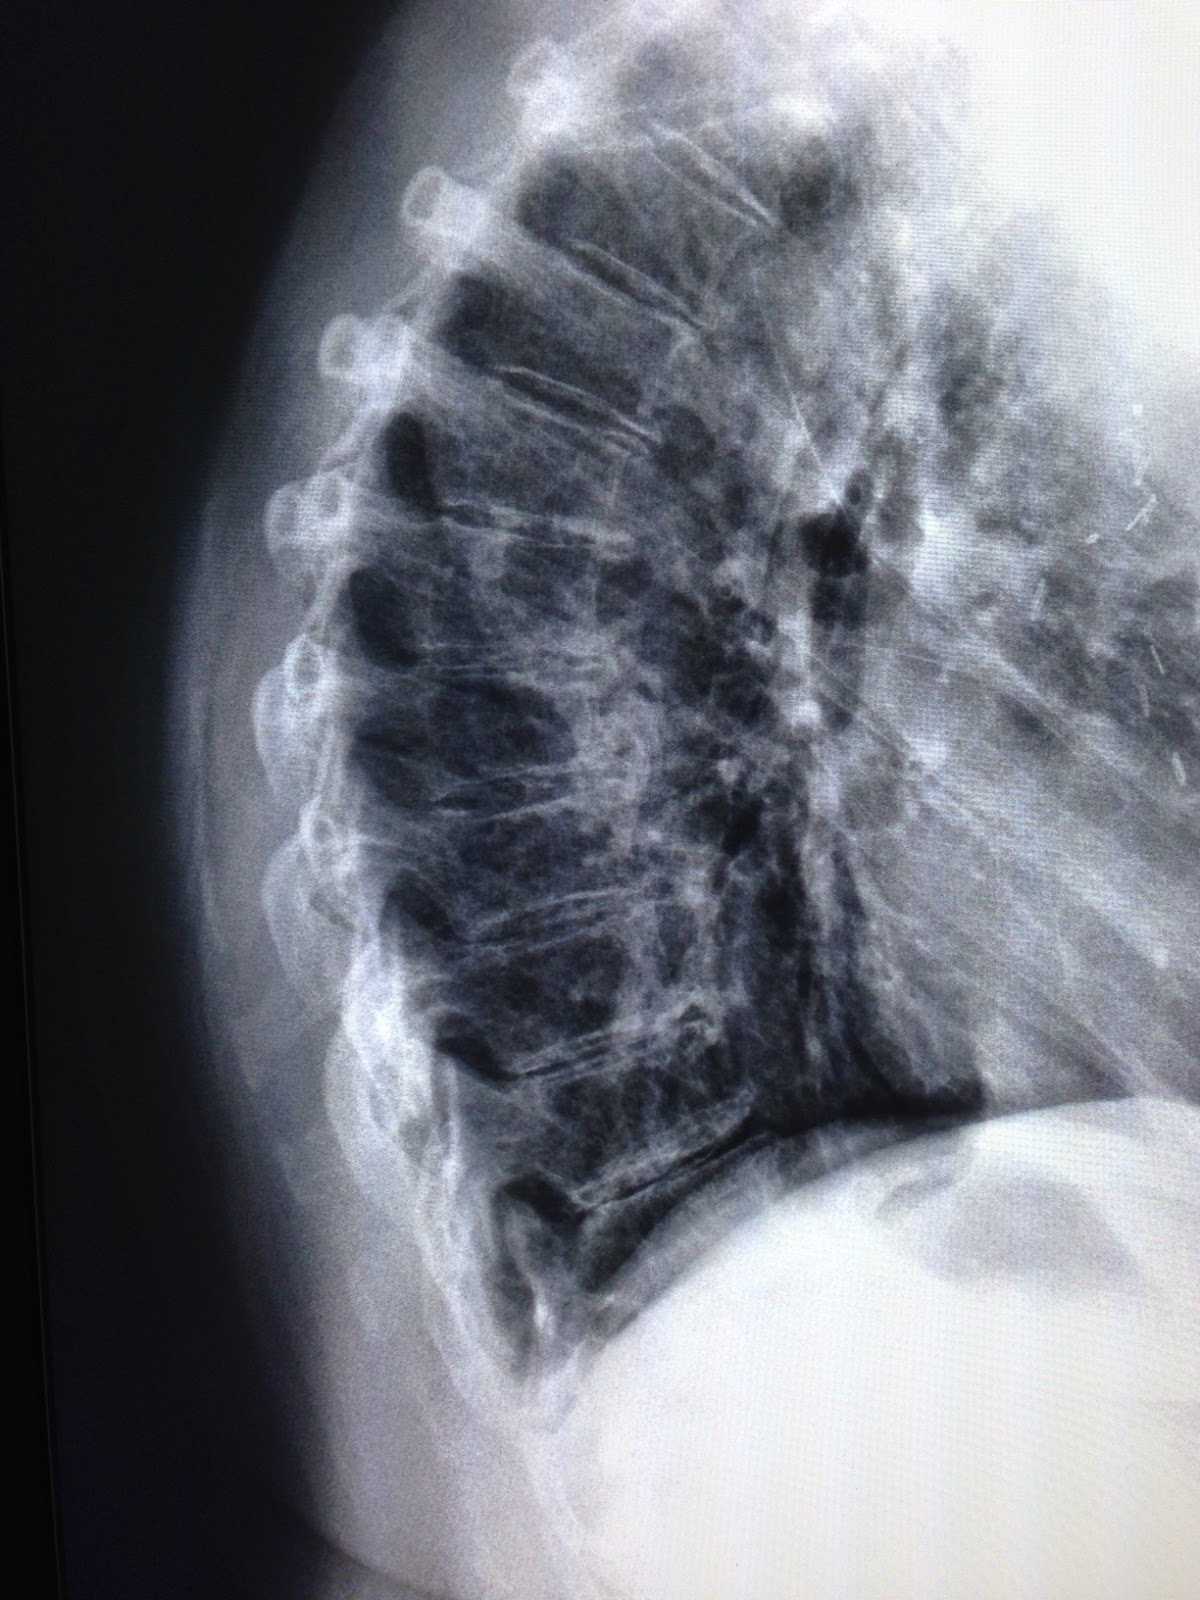

Purpose: To identify patients likely to present with a vertebral compression fracture.

Rule:

Roman et al., 2010:

1. Age > 52 years

2. No presence of leg pain

3. Body mass index < 22

4. Does not exercise regularly

5. Female gender

Stage of CPR Development: Derivation.

| Variables | Sensitivity | Specificity | +LR | -LR |

| 1 | 0.97 | 0.06 | 1.04 | 0.39 |

| 2 | 0.95 | 0.34 | 1.40 | 0.16 |

| 3 | 0.76 | 0.68 | 2.50 | 0.34 |

| 4 | 0.37 | 0.96 | 9.60 | 0.65 |

| 5 | 0.03 | 0.99 | 9.30 | 0.97 |

Henschke et al., 2009:

1. Female sex

2. Age > 70 years old

3. Significant trauma (major in young patients, minor in elderly patients)

4. Prolonged use of corticosteroids

| Variables | Sensitivity | Specificity | +LR |

| 1 | 0.88 | 0.50 | 1.8 |

| 2 | 0.63 | 0.96 | 15.5 |

| 3 | 0.38 | 1.00 | 218.3 |